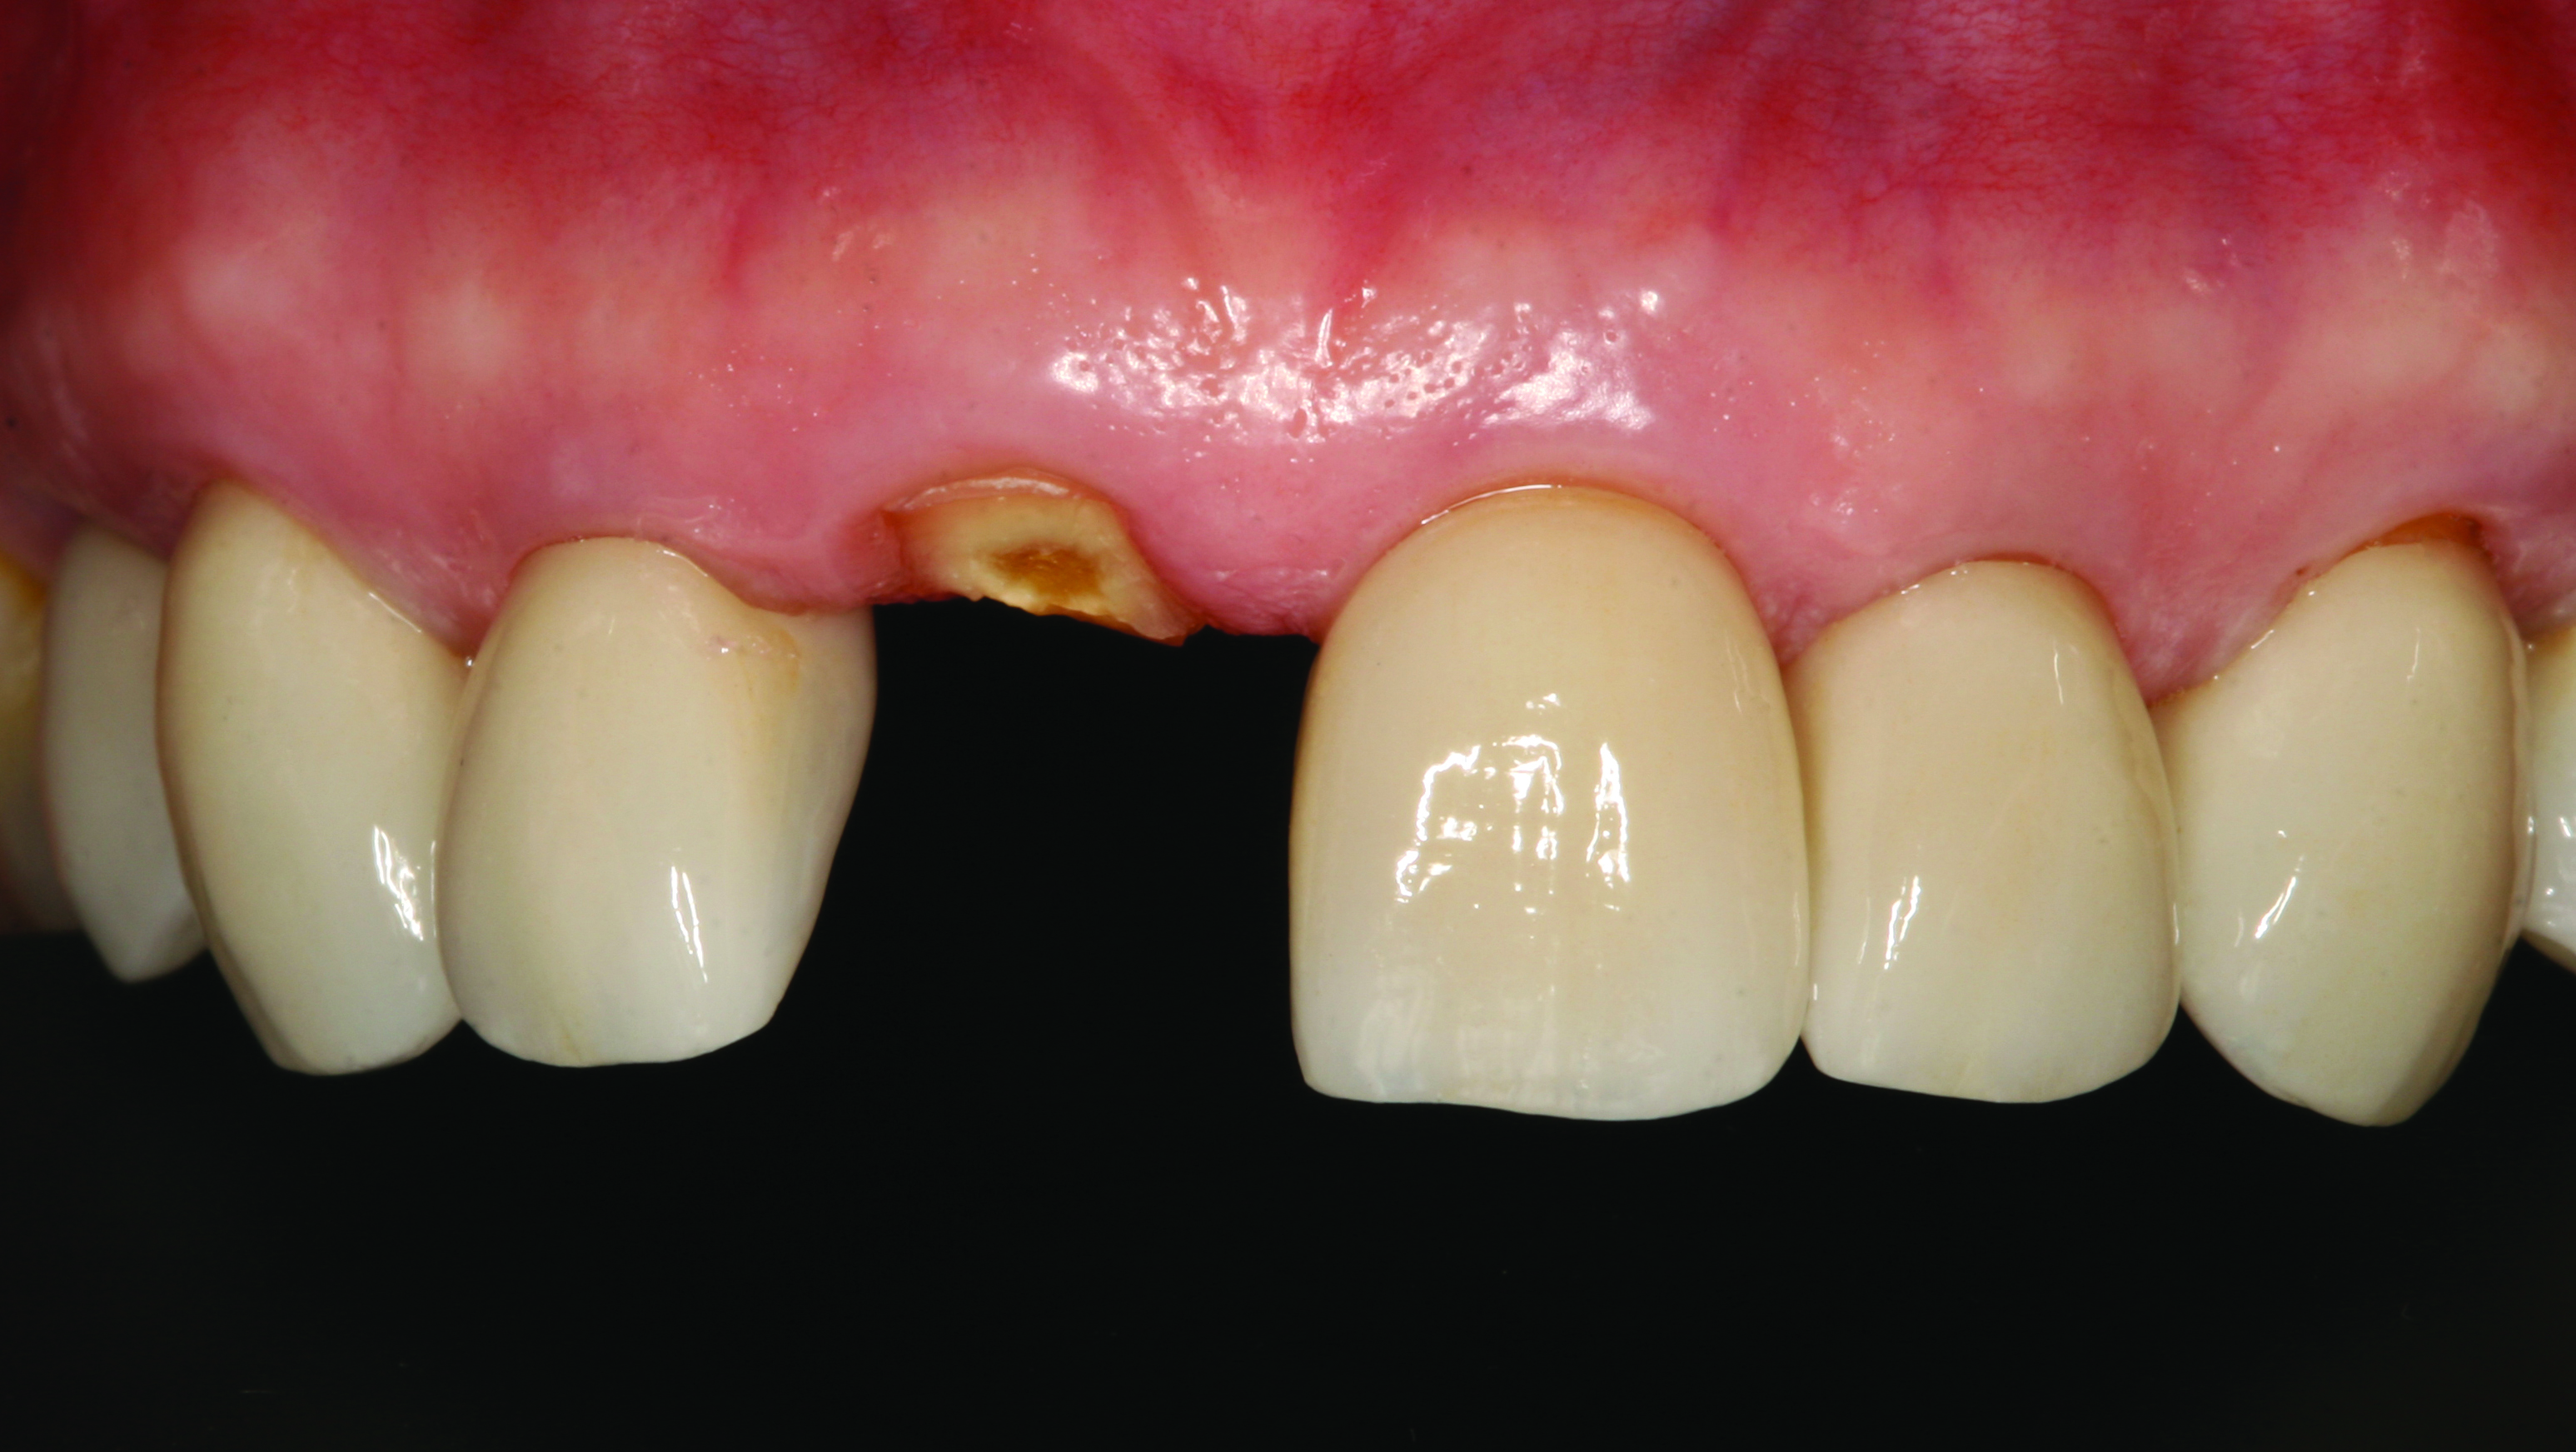

A 62-year-old woman presented on emergency, reporting having fractured her right central incisor (Figure 1). The area was asymptomatic and demonstrated no problems other than the embarrassment associated with the loss of her front tooth. Diagnostic records were made and an Essix retainer (essix.com) was fabricated to help alleviate her immediate esthetic concerns. Due to the lack of tooth structure incisal to the gingiva, the prognosis of the tooth was very guarded. Various options to restore this area were presented to the patient, leading to her ultimate choice of a dental implant. A diagnostic CBCT scan of the patient was attained and the patient left the office wearing the retainer.

Fig 1. Pre-operative situation of a fractured tooth No. 8.

Figure 1